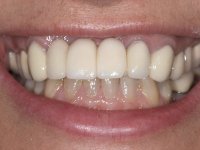

In view of the clinical situation, oral rehabilitation was proposed to improve the aesthetic appearance, but also to solve the lack of posterior teeth, seeking a functional and aesthetic rehabilitation. The plan included replacing the metal-ceramic bridge by a bridge with Zr infrastructure coated with coronary and gingival ceramics. The edentulous area of the first quadrant would be rehabilitated with 2 implants and a bridge of two elements. It was intended with this treatment plan, to recover the vertical dimension of the occlusion and to reshape the dental anatomy, thus creating a more natural aesthetic appearance.

Alginate impressions were made at both arches arcades, accompanied by intermaxillary registration relations and collecting information with facial bow facial bow. In the laboratory, a provisional bridge with 13 elements in autopolymerizable acrylic was built, in which a metallic reinforcement was included. Teeth 1.7 / 1.4 / 1.3 / 2.2 / 2.3 / 2.4 and 2.6 were used as pillars. The metal-ceramic bridge was removed after performing longitudinal cuts with diamond burs. The dental abutments were reprepared and the temporary bridge was relined in the mouth with self-curing acrylic. After confection of the provisional bridge, a gingival epithesis was made using composite resin with gingival tonality in order to function as a mock-up, which allowed the patient to preview the possibility of using gingiva shade ceramics in the final work. This option was approved by the patient. Subsequently, the placement of two implants in the first quadrant was planned and executed. The provisional monoblock was removed for placement of the implants, and after surgery was again cemented provisionally. After the osseointegration period, the impressions were made to the maxilla. In the anterior zone, impregnated gingival retraction cords were used, and in the posterior areas, kaolin paste was used. Implant printing utilized the open tray technique. The printing material used was soft and regular putty addition silicone, both fast-setting. In the laboratory, the model of provisional restorations and the gingiva epithesis mock-up served as orientation for waxing the infrastructure. The plaster work model and the waxing of the infrastructure were placed in a laboratory scanner and yielded a digital work model, in which the scanning of the waxed infrastructure was superimposed. This overlay facilitated the CAD design of the Zr infrastructure. Subsequently, the CAD drawing for a CAM milling process provided the Zr pieces. The infrastructure was pigmented with a pinkish coloration, which favors the subsequent placement of gum shade ceramic. During the modeling of the infrastructure, the need to increase the occlusal wear on tooth 1.4 was detected. This was done in the real working model cast and an acrylic wear control guide was created, which accompanied the proof of the infrastructures. Corrective wear and Zr parts test were performed in mouth. During the test, the color choice of the gum shade ceramic was reassessed. The treatment was finished in the laboratory, and after approval by the patient, was definitively placed in the mouth.